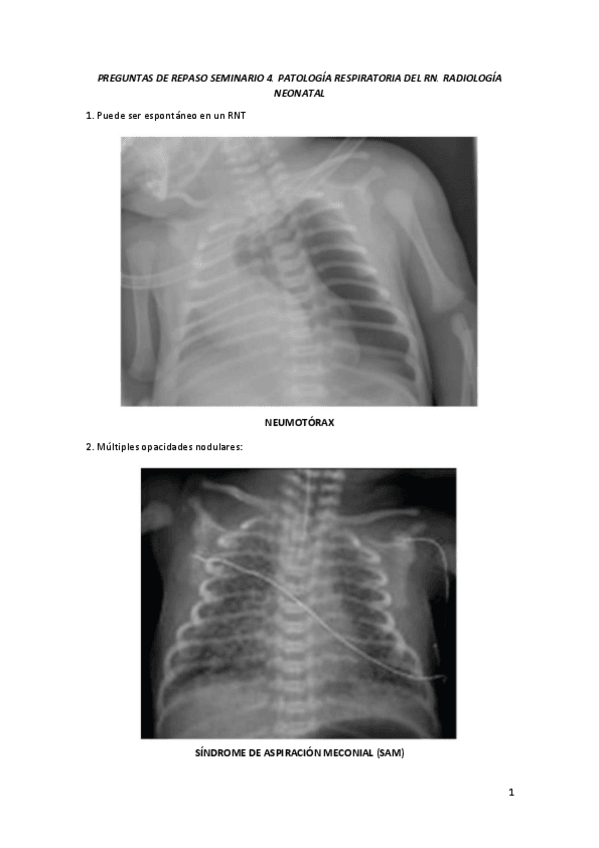

PREGUNTAS-DE-REPASO-SEMINARIO-4.-PATOLOGIA-RESPIRATORIA-DEL-RN.-RADIOLOGIA-NEONATAL.pdf